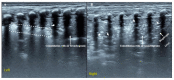

Results: We included 17 studies, reporting a total of 274 patients with M. pneumoniae, 30 with fungal infection and 213 with pulmonary tuberculosis (TB). Most of the studies on M. pneumoniae in children found a specific LUS pattern, mainly consolidated areas associated with diffuse B lines. The typical LUS pattern in TB consisted of consolidation and small subpleural nodes. Only one study on fungal disease reported LUS specific patterns (e.g., indicating "halo sign" or "reverse halo sign").